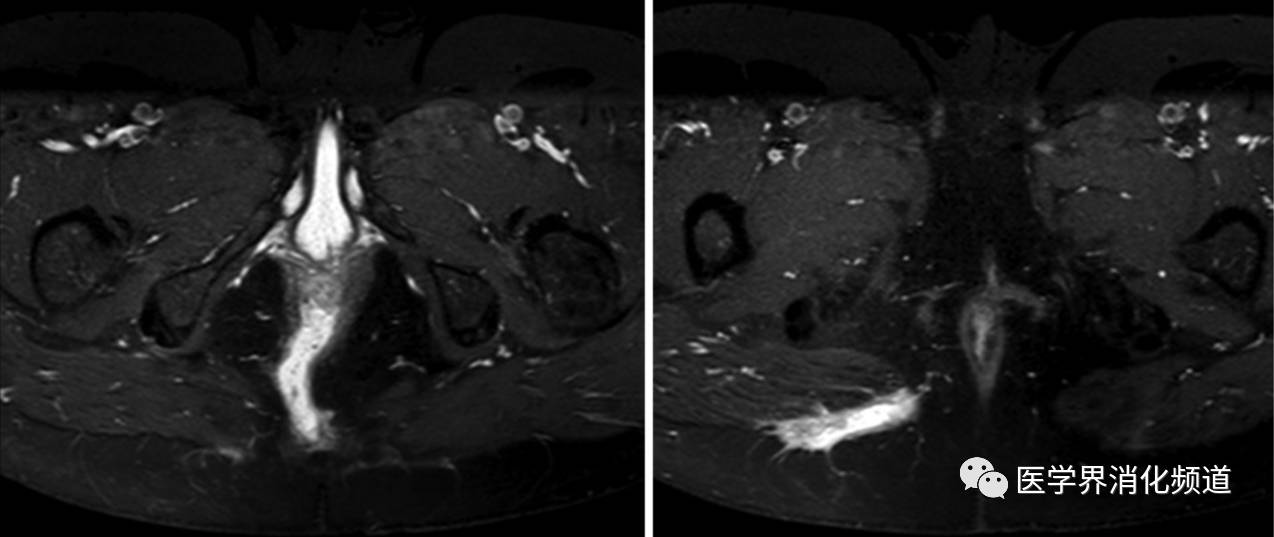

影像学检查在评估瘘管解剖学特征、排除脓肿等感染性疾病、制定治疗方案和监测治疗反应至关重要。复杂性肛瘘均应进行盆腔核磁共振检查(magnetic resonance imaging, MRI)(图1)。MRI在鉴别诊断肉芽组织和纤维化组织,诊断瘘管型脓肿具有高准确性,且无创伤、无辐射。MRI诊断特异性在76%-100%之间[11]。机器设备不普及和检查费用高限制了MRI广泛应用。

图1 经括约肌瘘。横截面,T1加权图像。(A)显示耻骨直肠肌下方高信号管道(长13cm)。(B)显示同一患者的瘘管延伸至臀大肌。